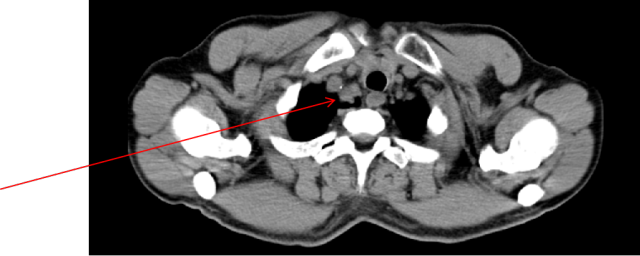

2024-09-13:胸+全腹(含盆腔)CT平扫:右肺尖胸膜下(Img 6/38)、右肺下叶内基底段胸膜下(Img 53/375)见软组织密度结节,较大者位于右肺下叶胸膜下,大小约 2.4×1.9cm。右肺尖、右肺下叶内基底段胸膜下软组织密度灶,较前新发,考虑转移灶;双肺结节,不除外转移,食管下段周围肿大淋巴结,较前增大;PD。

2024-09-13: